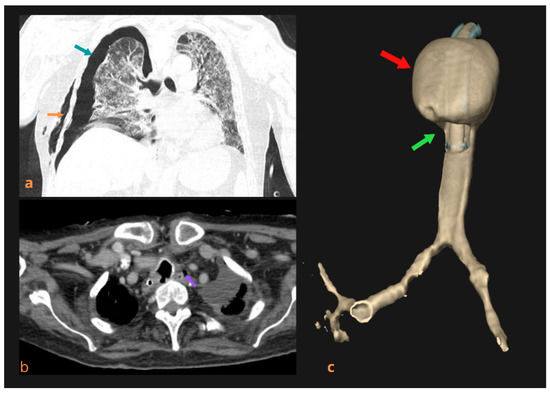

Figure 2.

Life-threatening complications caused by damage to the tracheal wall due to TM in the cuff area of the endotracheal tube or tracheostomy tube. Thoracic CT scan showing a right-sided pneumothorax (green arrow) and subcutaneous emphysema (orange arrow) (a). CT scan of a patient with a clinically (larger amount of air appeared in the nasogastric tube, along with abdominal distension and hyper-resonance on abdominal percussion, along with the appearance of food on the tracheostomy tube) and a bronchoscopically identified tracheoesophageal fistula. Axial plane showing pneumomediastinum (purple arrow) (b). A 3D view of the trachea with TM (red arrow) and interruption of the continuity of the membranous part of the posterior trachea wall in the cuff area (green arrow) (c).